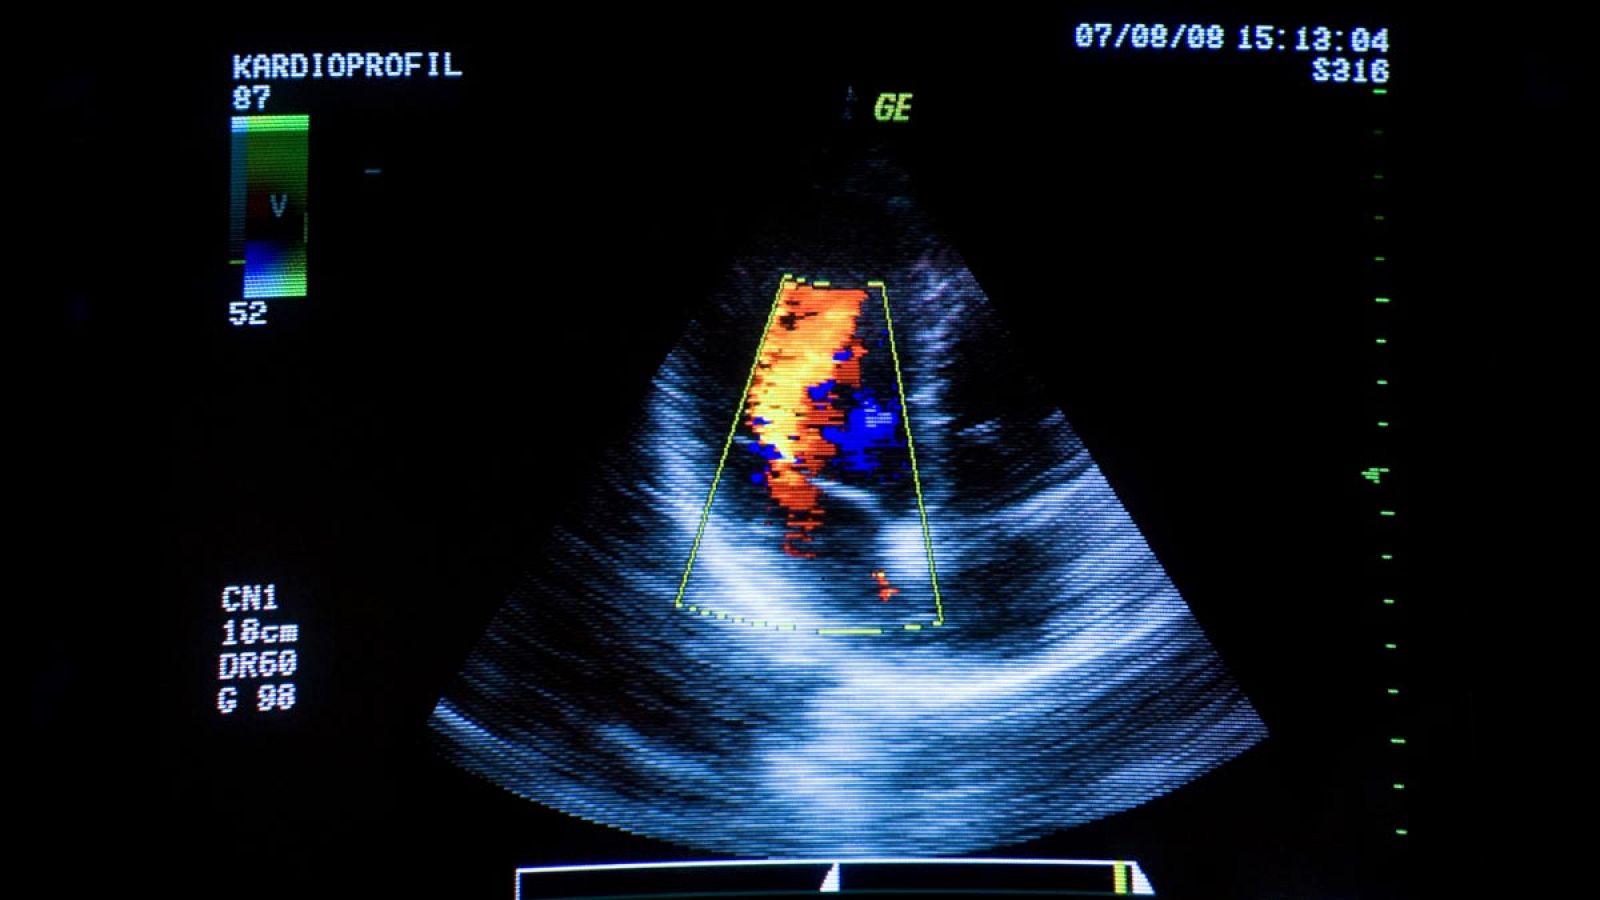

Imagen de archivo de una prueba cardiaca de diagnóstico.